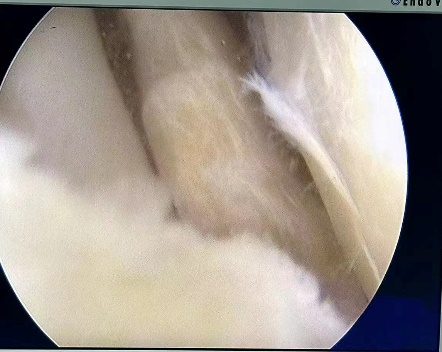

病例七:患者,女,36岁,因“左膝关节疼痛活动受限5天”入院。诊断:左膝外侧半月板撕裂;行左膝关节镜探查+滑膜清理+外侧半月板成形术;手术顺利,术后恢复良好,顺利出院。

左膝外侧半月板撕裂 术中关节手术图片